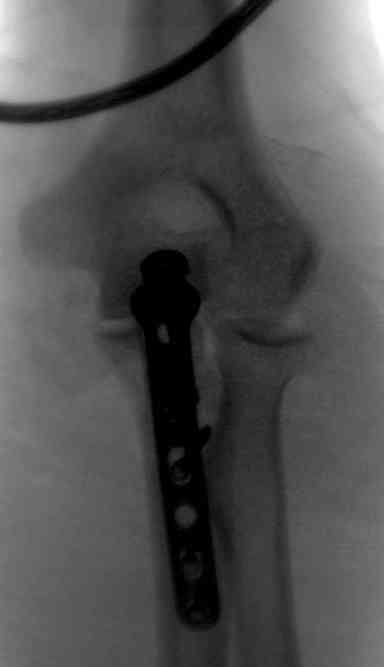

3 вариант

перелом с capitelum humerus и проксимальной трети улна